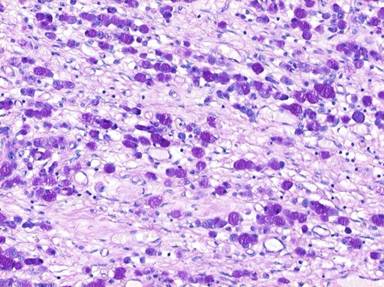

On histological analysis, an ill-defined lesion measuring 12 mm in maximum dimension was noted near the ampulla, extending to its anterior margin (Figure 1). The tumour measured 30 mm in maximum dimension within the duodenal submucosa, from where it ulcerated into the duodenal mucosa, surrounding blood vessels, the ampullary duct and the common bile duct (Figure 2). It infiltrated the duodenal muscularis propria and extended into the pancreatic parenchyma, reaching 16 mm from the superior mesenteric vein. Although there was extensive perineural invasion with infiltration of the duodenal mucosal and submucosal lymphatics, the pancreatic resection margin was not involved, and 0/13 peripancreatic and 0/10 greater curve lymph nodes were all free of tumour (T3N0M0). Microscopic appearances showed a poorly-differentiated signet-ring cell carcinoma, composed entirely of round cells containing intra-cytoplasmic mucin (Figure 3). Immunohistochemical staining was strongly positive for cytokeratin (CK) 7, CK20, CK8/18, CK19, CEA mono, CA 19-9, CA 125, MUC1 and MUC5AC. Tumour cells showed no expression for MUC2, MUC6, SMAD4, CDX2, ER and PgR. This immunohistochemical staining pattern is highly suggestive of signet-ring cell carcinoma of pancreatobiliary origin [3].

Figure 3. Higher magnification (DPAS, x200) reveals poorly-differentiated signet-ring cell carcinoma composed of single, non-cohesive, round and vacuolated cells containing intra-cytoplasmic mucin. |